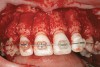

Figure 5c  Note lack of alveolar development from congenitally missing Nos. 24 and 25. Surgical procedures after 5 months of orthodontic alignment included single-tooth osteotomies Nos. 6 to 11 and Nos. 21 to 28 and buccal corticotomies on all other teeth. Anchorage plate was stabilized to piriform rim.

Figure 5c

Figure 5d  Note lack of alveolar development from congenitally missing Nos. 24 and 25. Surgical procedures after 5 months of orthodontic alignment included single-tooth osteotomies Nos. 6 to 11 and Nos. 21 to 28 and buccal corticotomies on all other teeth. Anchorage plate was stabilized to piriform rim.

Figure 5d

Figure 5e  Anchorage plate was stabilized to piriform rim (E through H). Final result 12 months postsurgery (F). There is significant lateral dentoalveolar expansion of arches and alveoloskeletal correction in maxillary and mandibular anterior regions. Alveolar bone volume was increased in lower anterior to create optimal implant sites and establish ideal interincisal function and stability.

Figure 5e

Figure 5f  Anchorage plate was stabilized to piriform rim (E through H). Final result 12 months postsurgery (F). There is significant lateral dentoalveolar expansion of arches and alveoloskeletal correction in maxillary and mandibular anterior regions. Alveolar bone volume was increased in lower anterior to create optimal implant sites and establish ideal interincisal function and stability.

Figure 5f